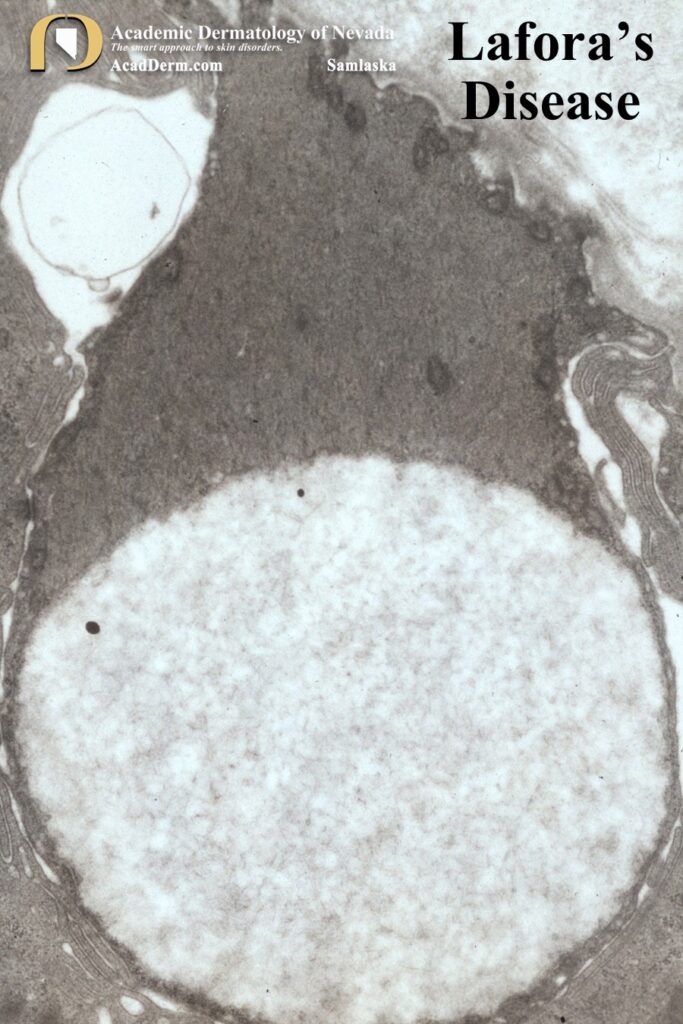

The images above demonstrate Lafora bodies and the filamentous and fine granular matrix within non-membrane-bound inclusion bodies within myoepithelial cells (electron micrograph X 23,700).